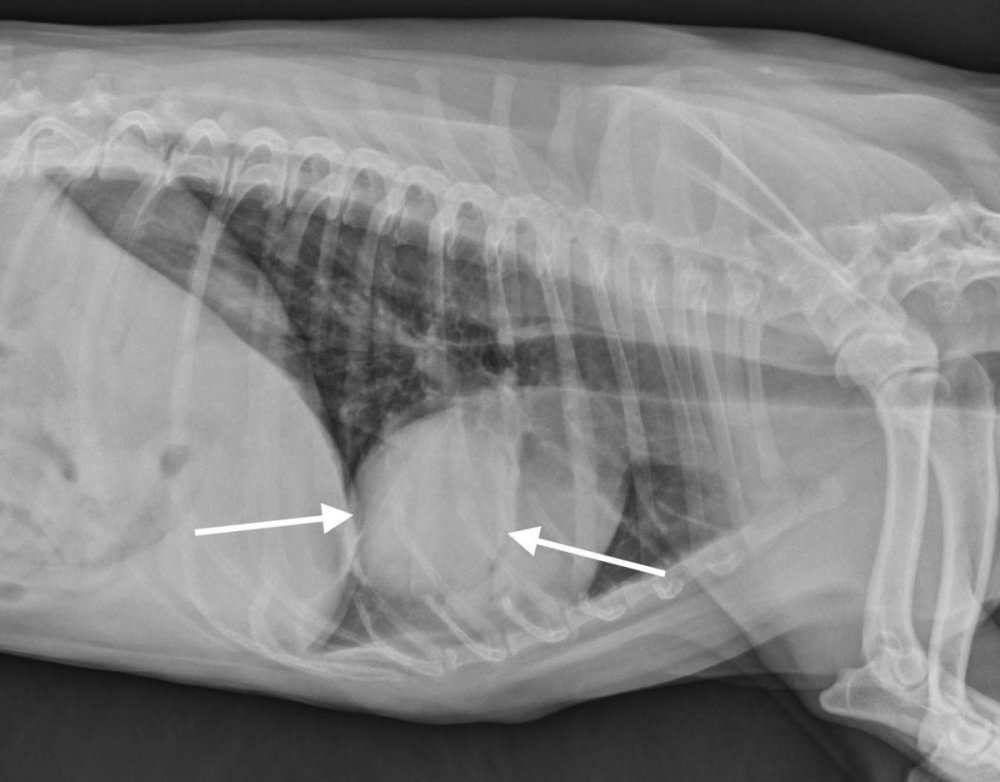

Diagnosis usually happens in layers. A vet will start with a physical exam and history, then move to imaging. Chest X-rays are often the first step, and they can show lung masses, changes in lung pattern, and sometimes enlarged lymph nodes.1, 7

A CT scan can provide a much clearer map of what is happening in the chest, including the size and location of a mass, whether lymph nodes look involved, and whether there are multiple lesions that might suggest spread.1, 7

Treatment depends on whether the tumour is solitary, whether it has spread, what type it is, and your dog’s overall health. In many dogs with a single primary lung lobe tumour, surgery to remove the affected lung lobe (lung lobectomy) is considered the treatment of choice, especially when there is no evidence of spread.1, 7